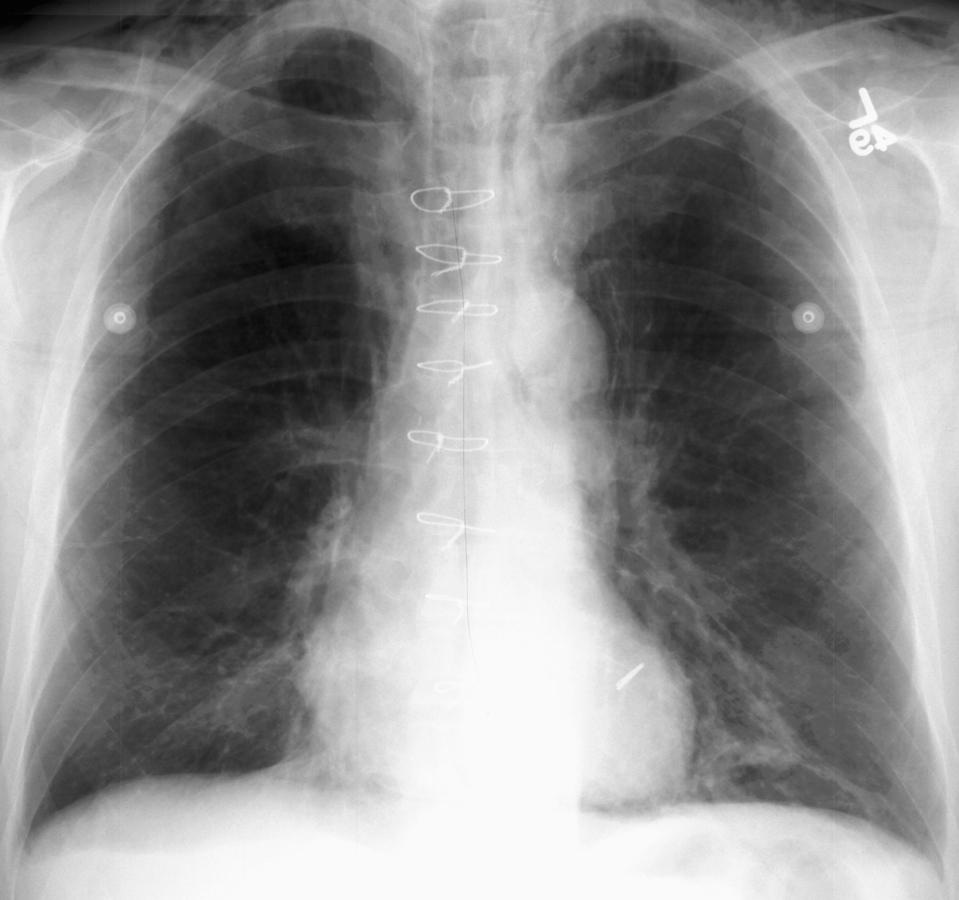

Pneumomediastinum

In the intubated patient the most likely source of air in the mediastinum is pulmonary interstitial air dissecting centripetally. Air in the mediastinum may also originate from tracheobronchial injury or air dissecting through fascial planes from the retroperitoneum. A sudden increase in thoracic pressures (e.g. blunt trauma) may also cause alveolar rupture and consequently pneumomediastinum.

Findings include; streaky lucencies over the mediastinum that extend into the neck, and elevation of the parietal pleura along the mediastinal borders.

Pneumomediastinum often dissects up into the neck. This helps to distinguish it from pneumopericardium that, unlike pneumomediastinum, can extend inferior to the heart.

Causes of pneumomediastinum include; asthma, surgery (post-op complication), traumatic tracheobronchial rupture, abrupt changes in intrathoracic pressure (vomiting, coughing, exercise, parturition), ruptured esophagus, barotrauma, and smoking crack cocaine.

Pneumomediastinum should be distinguished from pneumopericardium and pneumothorax. In pneumopericardium, air can be present underneath the heart, but does not enter the neck.

Continuois diaphram sign